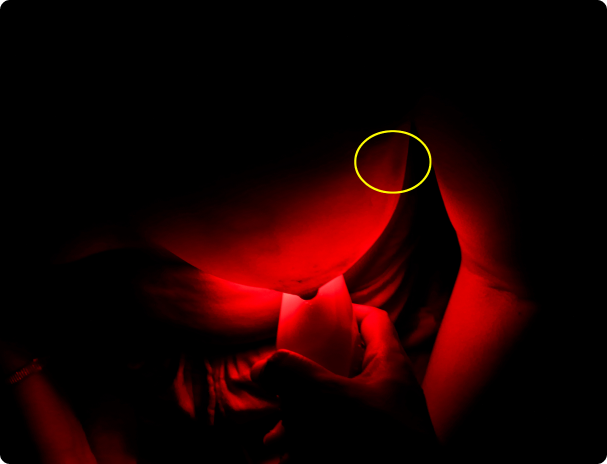

The core component of iSCANBREAST, this device is designed for easy and effective self-examination of the breasts. With its advanced LED light technology, the iSCANBREAST Device provides a clear view of the internal breast structure, aiding in early detection and promoting breast health awareness.

iSCANBREAST works by utilizing advanced LED light technology to provide a clear view of the internal structure of the breasts.

The device emits a gentle yet penetrating light that allows users to visualize breast tissue, facilitating early detection of potential abnormalities.

Yes, iSCANBREAST is designed to be user-friendly. Simply charge the device, turn it on, and place it on your breasts to conduct a self-examination. The device activates upon contact with the skin, making it convenient and accessible for regular use.